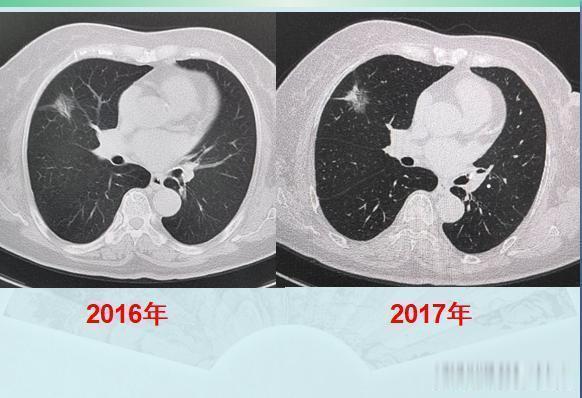

第一位,乳腺癌手术后2年又查出肺癌,拖了两年才手术,很成功!

这是一位71岁的老太太,乳腺癌手术后定期体检,又发现右肺磨玻璃结节灶,大小2.0厘米: